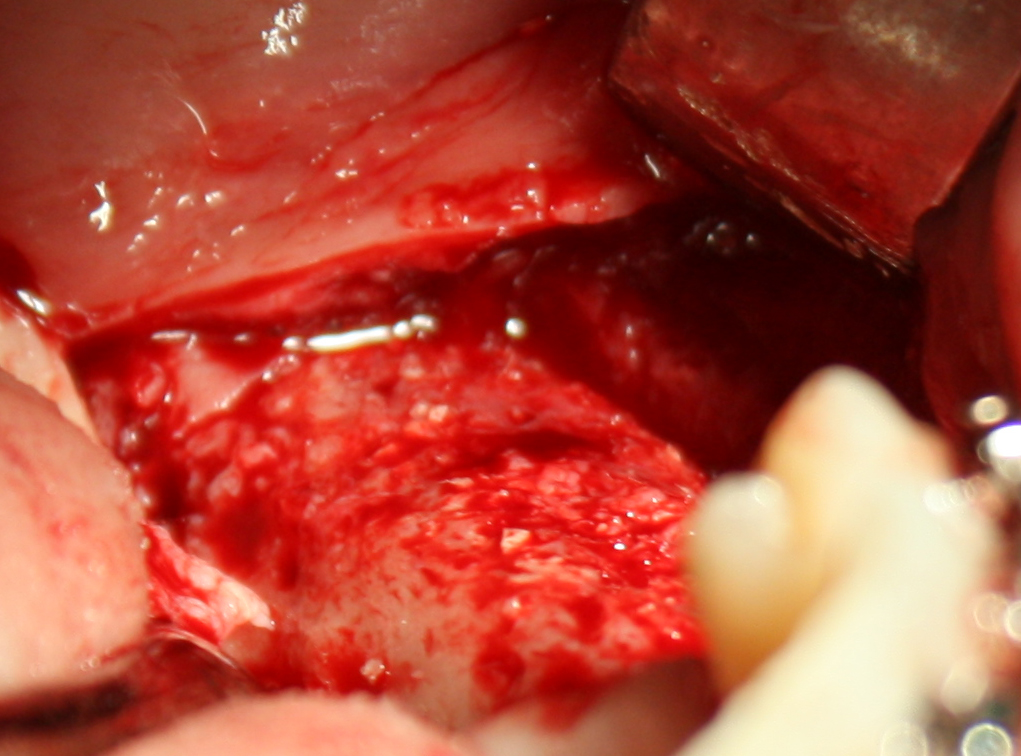

Что же касается нерезорбируемых мембран… Было дело, работал с Gore-Tex (дорого, очень дорого), титановыми сетками (заколебался потом доставать) и тефлоновыми Cytoplast:

результат:

или

с трудом выковыриваем сетку и ищем имплантат:

чтобы поставить формирователь: